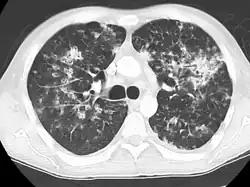

Tuberculosis of the lungs

Testing for miliary tuberculosis is conducted in a similar manner as for other forms of tuberculosis, although a number of tests must be conducted on a patient to confirm diagnosis.[3] Tests include chest x-ray, sputum culture, bronchoscopy, open lung biopsy, head CT/MRI, blood cultures, fundoscopy, and electrocardiography.[9] The tuberculosis (TB) blood test, also called an Interferon Gamma Release Assay or IGRA, is a way to diagnose latent TB. A variety of neurological complications have been noted in miliary tuberculosis patients—tuberculous meningitis and cerebral tuberculomas being the most frequent. However, a majority of patients improve following antituberculous treatment. Rarely lymphangitic spread of lung cancer could mimic miliary pattern of tuberculosis on regular chest X-ray. [14]

A case of miliary tuberculosis in an 82-year-old woman: